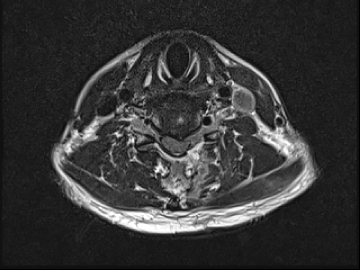

고주파수핵성형술

2017.08.07

ㆍ환자 동의를 받은 자료이며, 이미지 사진은 실물과 다를 수 있습니다.

ㆍ모든 자료는 새움병원 자료입니다.